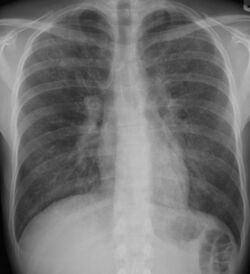

Pneumocystis pneumonia can present with interstitial lung disease, as seen in the reticular markings on this AP chest x-ray.

Chest radiography is usually the first test to detect interstitial lung diseases, but the chest radiograph can be normal in up to 10% of patients, especially early in the disease process.[13][14]